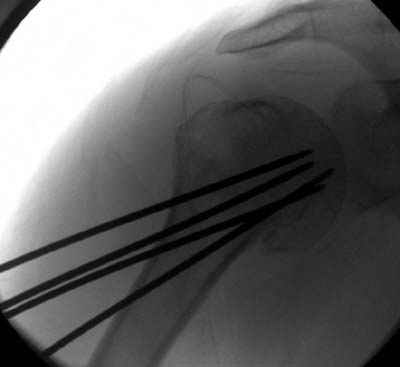

Женя, а как ты водишь спицы, в смысле, как делаешь входное отверстие, и как в него проводишь V-спицу? А то о дна из спиц, та, у которой не дошла до головки одна палочка буквы V, как-то выглядит на рентгенограмме, как будто или через очень большое отверстие введена, или каждая половинка через отдельные отверстия.

Мне кажется, проблема в том, что не все концы спиц зашли в головку, и зашедшие - недостаточно далеко прошли.

Спицы провожу по передней и задней поверхностям плечевой кости через 4,5 мм отверстия на разных уровнях.

Уточни - обе части буквы V вводишь в одно отверстие? А то по снимкам выглядит, что в разные.

V-спица проводится через 4,5 мм отверстие. Видимо, из-за разной длины вторая половина спицы *пролетела* мимо отверстия, что и привело к вторичному смещению костных фрагментов.